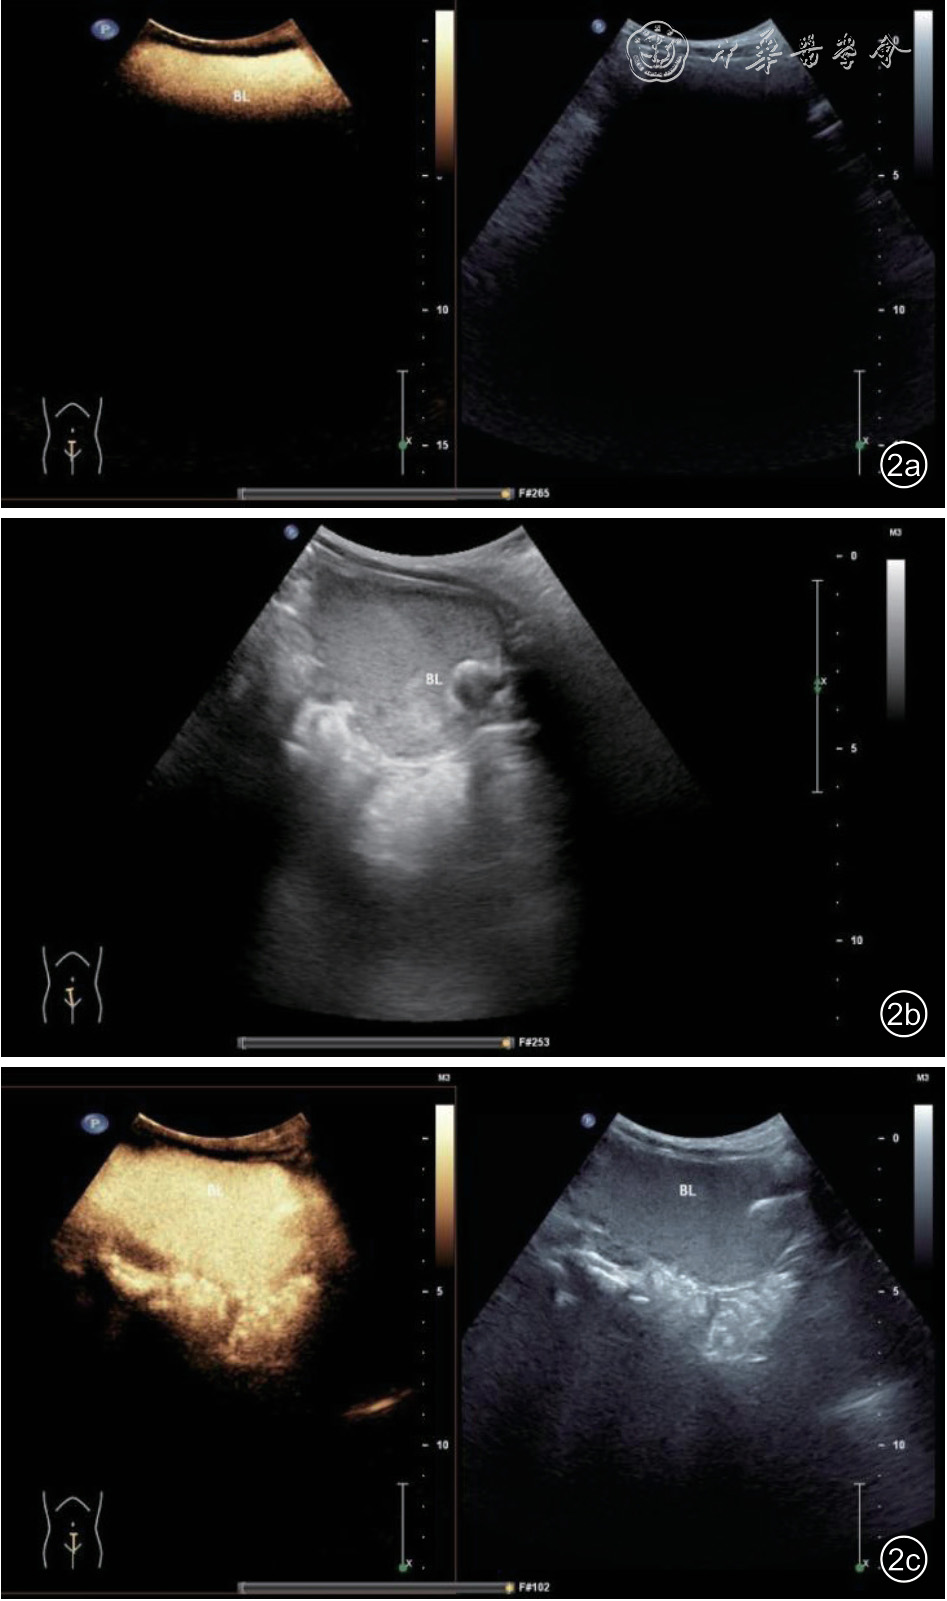

复旦大学附属儿科医院于2021 年12 月将CeVUS 造影方法由传统方法改为改良方法,传统方法为经导尿管注入生理盐水,待膀胱较充盈后,单次注入SonoVue 造影剂1 ml,此时膀胱内造影剂声影往往过于明显,需要通过机械爆破,或将图像转至机械指数较高的二维图像进行爆破数秒,再次进入造影模式后膀胱轮廓才逐渐显示清晰(图2)。

图2 排泄性尿路超声造影传统方法注入造影剂及爆破后超声图像。图a 为注入造影剂后声影明显,此时为低机械指数(MI 为0.06);图b 为图像转至机械指数较高(MI为1.3)的二维图像,爆破造影剂;图c 为爆破数秒后再次进入造影模式,膀胱轮廓逐渐显示清晰,可观察膀胱后方输尿管开口处